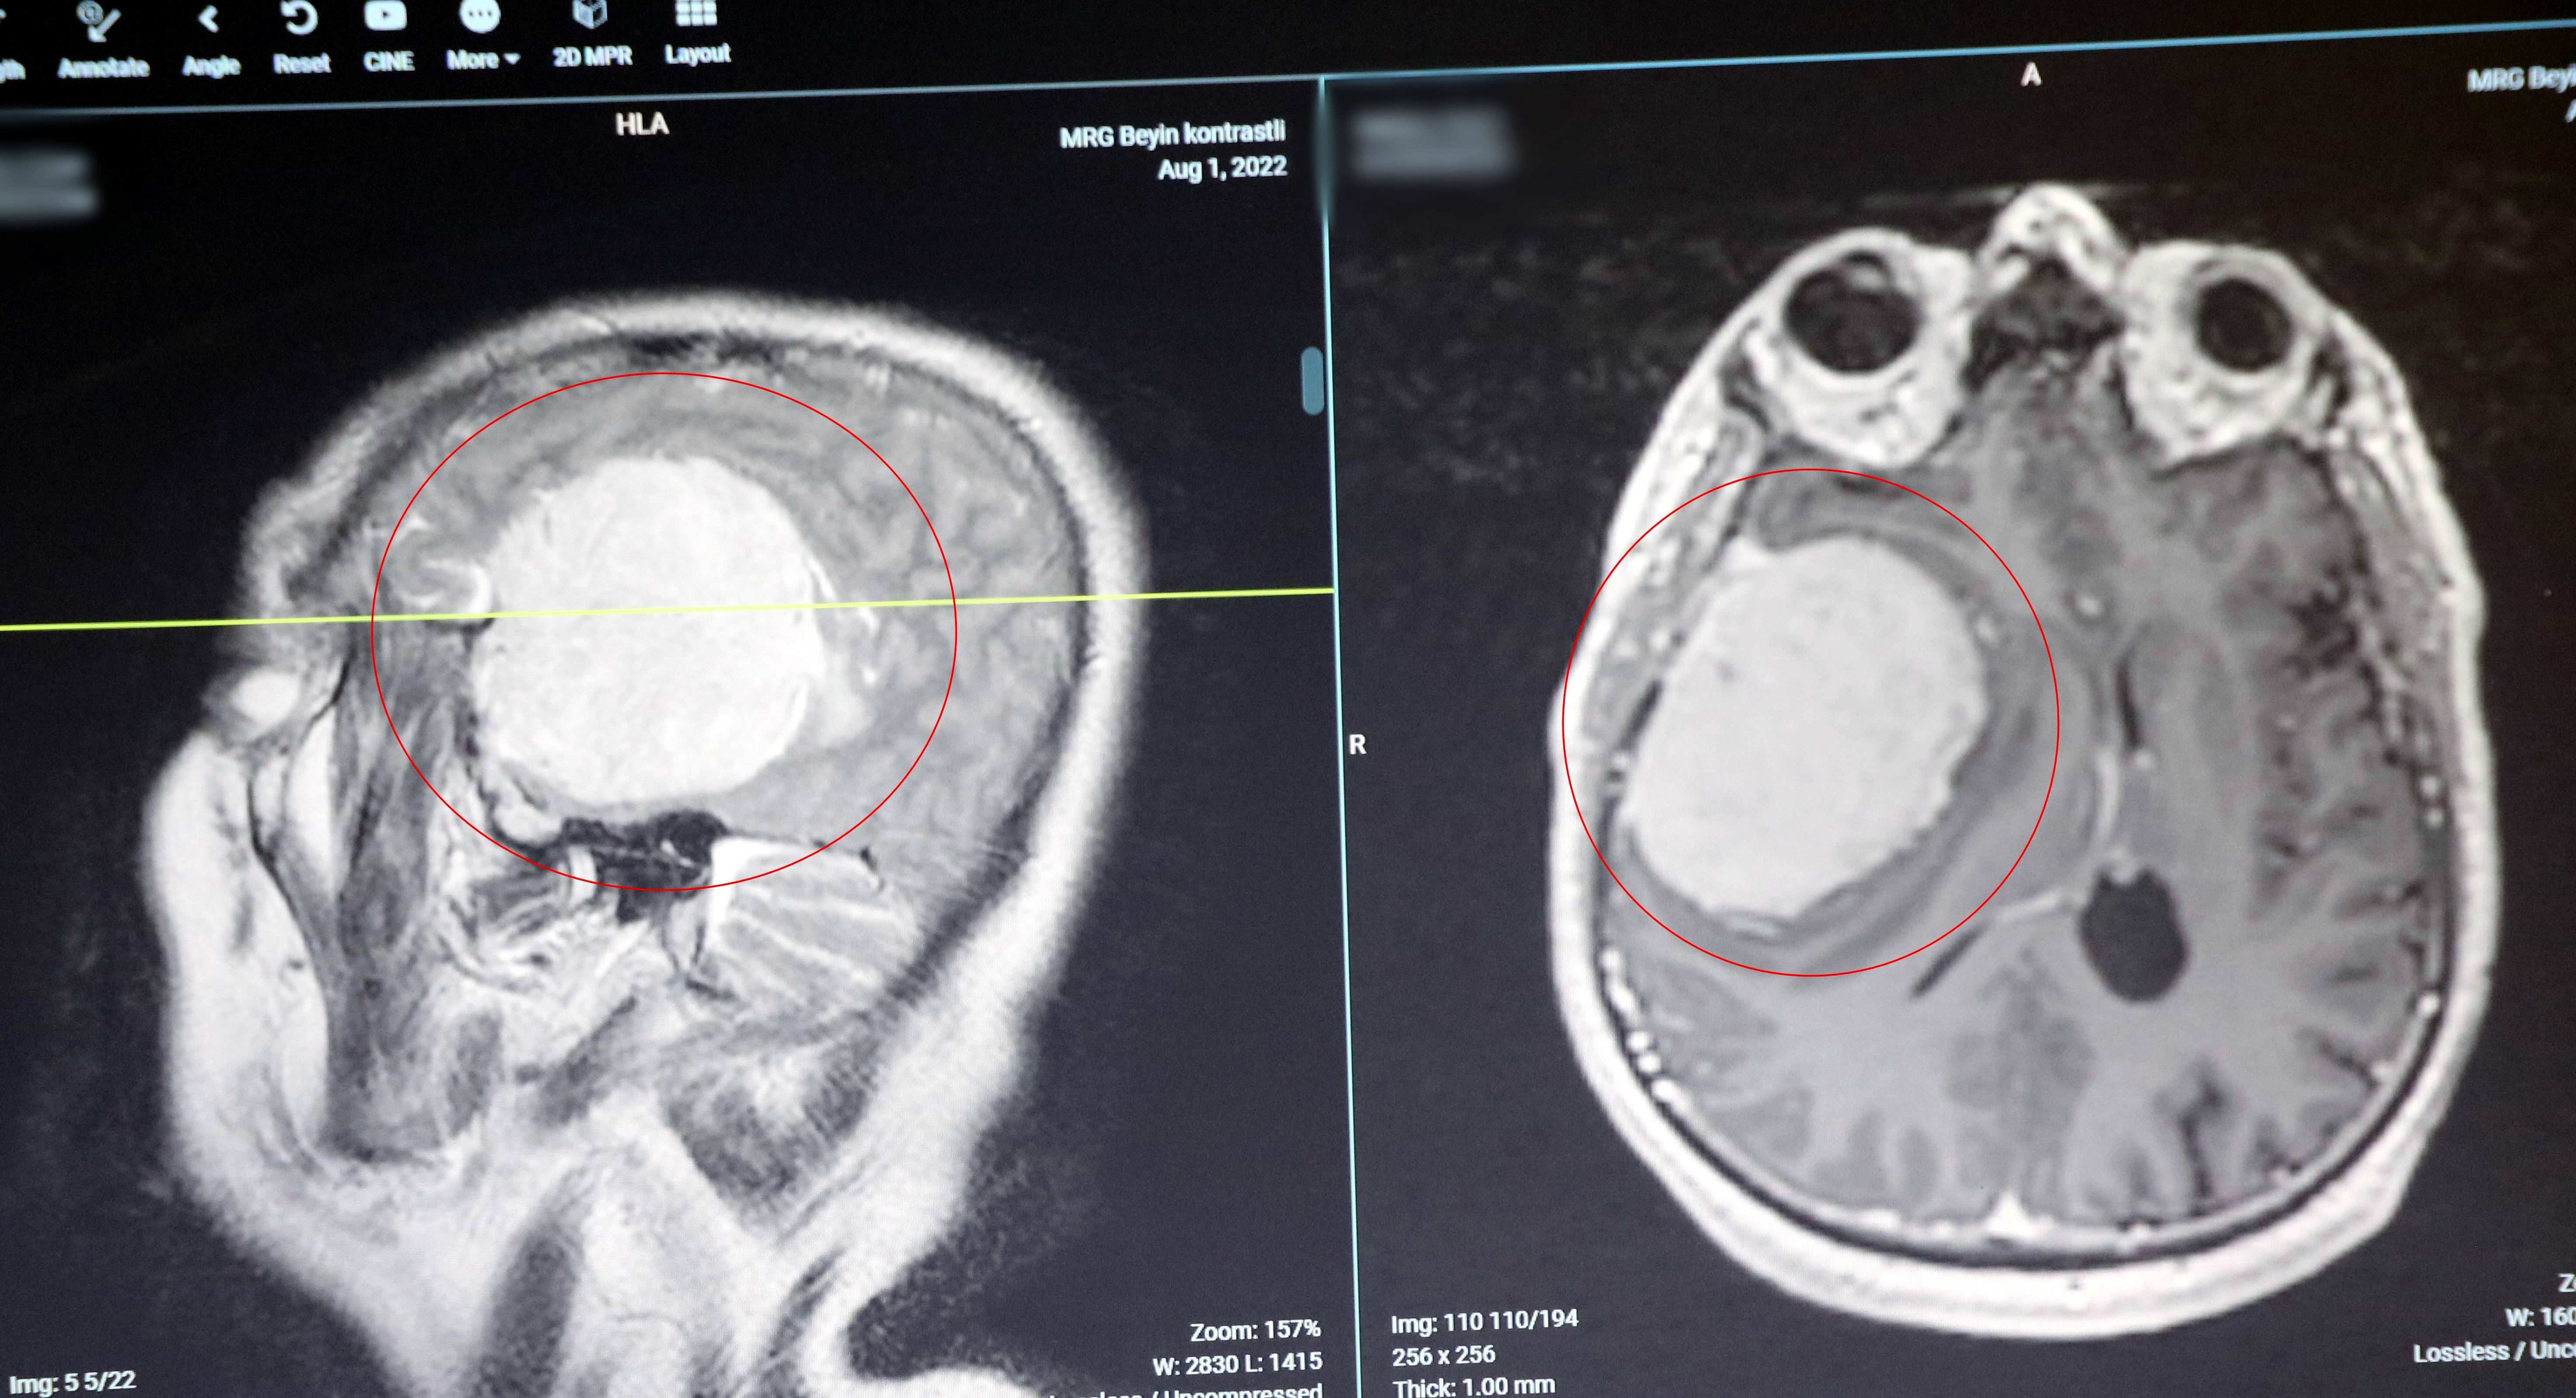

Tümörlerin 2’ye ayrıldığına değinen ve iyi huylu tümörlerde cerrahi müdahalenin kesin çözüm olduğunu vurgulayan Doç. Dr. Kuruoğlu, “Tümörler birincil yani beynin kendinden kaynaklanan tümörler ve ikincil tümörler dediğimiz ise vücudun herhangi bir yerinde çıkan bir tümörün beyne sıçraması ile meydana gelmesidir. İkincil tümörler de kötü huylu tümör olarak geçer. Birincil, beynin kendinden kaynaklanan tümörler de iyi ve kötü huylu olarak 2’ye ayrılır. İyi huylu tümörlerde cerrahi kesin çözümdür. Tümör çıkartılır ya da bir kısmı çıkartılır. Bu tümörlerde, kitle çıkarıldığında hastada bir daha tümör görüşmesi görmeyiz. Kötü huylu tümörlerde tümör çıkarıldıktan sonra hastaya ikincil tedavi olarak ışın, kemoterapi ve ilaç tedavisi gibi ek tedaviler vermek gerekir. Özellikle iyi huylu tümörler genellikle çok büyüyünce fark edilir. Beyin içinde oluşan tümör direkt bir ağrı oluşturmaz. Beynin ağrı duyusu yoktur. Tümör çok büyüyüp beyin zarını etkileyince hasta baş ağrısı hissetmeye başlar. O yüzden iyi huylu tümörler çok büyümeden bulgu vermeyebilir. Her baş ağrısının altından beyin tümörü çıkmaz ama baş ağrısı olan, daha önce bir hastalığı olmayan insanlar mutlaka görüntüleme yöntemi ile kontrol edilmelidir” şeklinde konuştu.

Bazı beyin tümörlerinin hastanın sağlığına olumsuz etki etmediğini belirten Enis Kuruoğlu, “Hastada tümör tespit ettiğimizde radyolojik olarak da iyi huylu olup olmadığını gözlemliyoruz. Eğer tümör fazla büyük değilse ve hastanın sağlığına risk oluşturmuyorsa 5-10 yıl sonra cerrahi uygulamadan takip yapabiliyoruz. Tümörde büyüme olursa çıkartılabiliyor. Kötü huylu tümörlerde ise geç kalınmaması gerekiyor. Hastada tümör tespit edildiği zaman mutlaka patolojik tanı alınması gerekiyor. Hatta tümör çıkarılabilecek gibi ise çıkarılması gerekiyor. Tümör kötü bir yerde, çıkarılması imkansız bir yerde ise, hasta ameliyattan sonra yatağa bağımlı kalacak, bilincini kaybedecekse küçük bir biyopsi alıp tümörün adını koyarak tedavi yöntemini belirliyoruz. Bunlara da ışın, gamma knife (odaklanmış ışınların hedef dokuya tek bir seferde verilmesi), kemoterapi tedavileri yapılabiliyor. Gelişen teknoloji ile birlikte kötü huylu tümörlerde de çok iyi sonuçlar alabiliyoruz” ifadelerini kullandı.